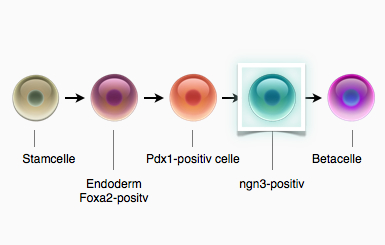

Figur 33. Forskerne har endnu ikke lavet en fuldt differentieret betacelle i laboratoriet. Det er dog lykkedes at lave umodne betaceller, der svarer til cellerne i et 6-9 uger gammelt foster. Alle cellerne er beskrevet ved en bestemt transkriptionsfaktor, som skal være udtrykt, for at cellen kan videredifferentiere sig mod en betacelle. Det er lykkedes forskerne at lave stamceller til neurogenin3-positive celler (ngn3), hvilket ville være et vigtigt skridt på vejen mod at danne fuldt funktionelle betaceller.

Det er endnu ikke lykkedes forskerne at lave fuldt funktionelle betaceller fra stamceller, men et stort gennembrud kom med transplantationen af stamceller differentieret til celler, der er et forstadie til betaceller. Cellerne er således differentieret til det stadie hvor de udtrykker neurogenin3, hvilket svarer til cellerne i et 6-9 uger gammelt foster. Det er endnu ikke lykkedes forskerne at finde de signalstoffer, der kan lave neurogenin3-positive celler om til betaceller. Cellerne i deres umiddelbare form, udviste kun meget få ligheder med betaceller, og kunne ikke bidrage til at opretholde et normalt blodsukker. Alligevel indopererede forskerne cellerne i mus med diabetes. Det viste sig, at cellerne modnede i musen, og efter 3 måneder var de differentierede til funktionelle menneske-betaceller. Det vil altså sige, at de udifferentierede celler der indsprøjtes, påvirkes af de signalstoffer, der findes i musen. Herefter differentierer de sig i den rigtige retning: til betaceller. Cellerne, der var et forstadie til betaceller, kunne altså bruges til at helbrede musen for diabetes.